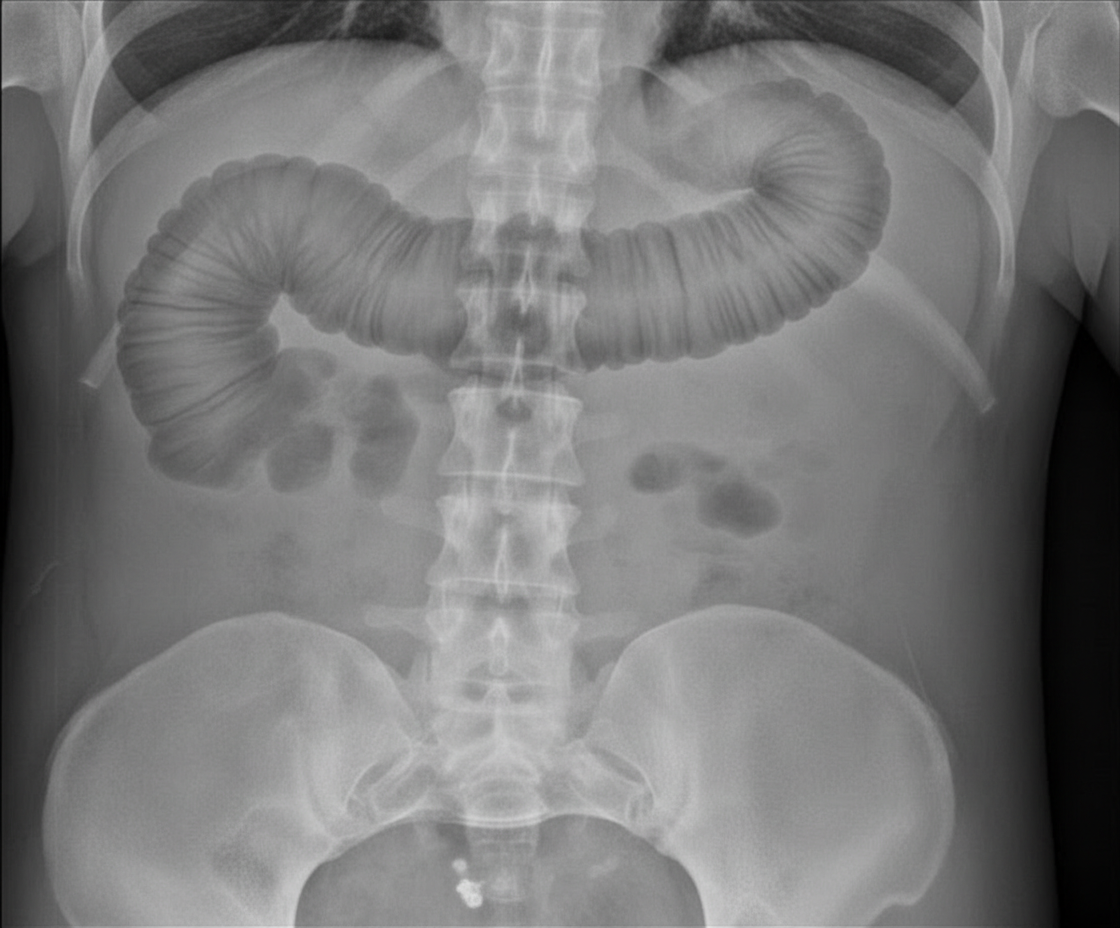

A 30-year-old man presents with abdominal pain and fever for one day. He has history of diarrhea for last several months which contains blood. What is the diagnosis?

Explanation: ***Toxic megacolon*** - The patient's history of **bloody diarrhea** for several months, followed by acute abdominal pain and fever, is highly suggestive of **inflammatory bowel disease (IBD)**, which is a common underlying cause of toxic megacolon. - The imaging shows **colonic dilatation (megacolon)**, supporting the diagnosis of toxic megacolon, an acute severe complication of inflammatory conditions of the colon. - Toxic megacolon is defined as **total or segmental colonic dilatation >6 cm** with systemic toxicity in the setting of severe colitis. *Pneumatosis intestinalis* - This condition is characterized by the presence of **gas in the bowel wall** and doesn't typically present with the specific history of chronic bloody diarrhea and acute fever leading to megacolon. - While it can occur in severe inflammatory conditions, the primary features of the clinical vignette and image point more directly to toxic megacolon. *Cecal volvulus* - A cecal volvulus would primarily present with features of **bowel obstruction**, often acute in onset, and typically not with a long history of bloody diarrhea directly preceding the acute event. - Imaging for cecal volvulus would show a **distended, air-filled cecum** often displaced from its normal anatomical position, which is not the predominant finding here. *Intestinal perforation* - Intestinal perforation would cause severe, acute abdominal pain, usually with signs of **peritonitis** and would typically show **free air under the diaphragm** on upright radiographs. - While chronic IBD can lead to perforation, the image primarily demonstrates colonic dilatation rather than obvious free air, and the initial diagnosis is toxic megacolon which can precede perforation. *Fulminant colitis* - While this patient does have severe colitis as the underlying condition, the presence of **marked colonic dilatation (>6 cm)** with systemic toxicity specifically defines toxic megacolon. - Fulminant colitis refers to **severe inflammation without the megacolon component**, with patients having >10 bloody stools per day, continuous bleeding, and systemic toxicity. - The imaging findings of significant colonic dilatation distinguish toxic megacolon from fulminant colitis.